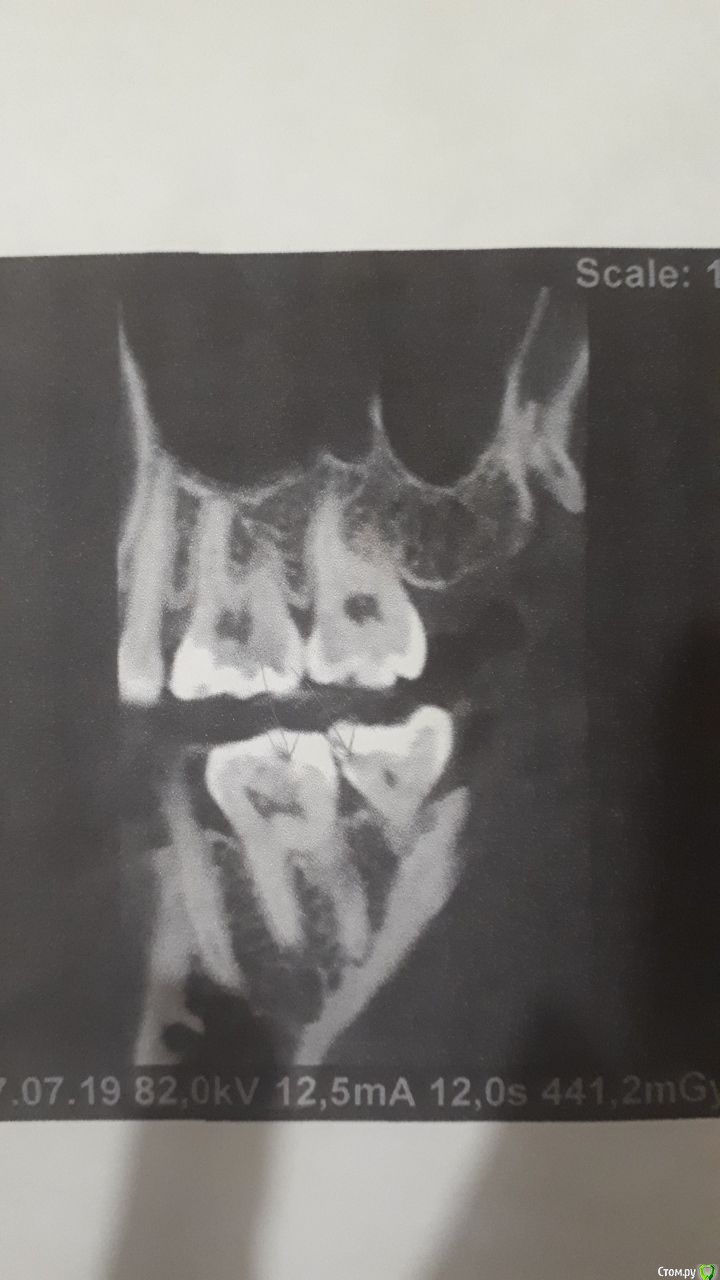

Яковлева Ксения Опубликовано 28 июля, 2019 Поделиться Опубликовано 28 июля, 2019 (изменено) Здравствуйте, уважаемые врачи! 3 недели назад мне запломбировали глубокий кариес в 6 и 7 нижних зубах с правой стороны. До этого эти зубы не беспокоили и не болели. И вот уже 3 недели меня беспокоют ноющие боли. Болит как в течение дня, так и вечером. Когда ем, то твердую пищу больно пережевывать этой стороной, Но болит терпимо. Стоматолог, который пломбировал, считает что так реагирует именно 7 зуб. Он также чувствителен на холодную пищу, на горячее не реагирует. Пломбу уже дважды подпиливали по прикусу, покрывали специальным составом для снижения чувствительности. Я также принимала нимесил в течение 5 дней по рекомендации врача для снижения боли и чистила зубы Сендодином. По рентгену стоматолог сказал, что все хорошо, но если будет и дальше так зуб беспокоить, то стоит его депульпировать (рентген прилагаю). 27.07.2019 я пошла в частную поликлинику, где мне сделали прицельную компьютерную томографию, которая показала, что пломбы как бы не плотно прилегают к зубу. Стоматолог в частной клинике предложил перелечить пломбы. После приема вечером правая сторона разболелась сама по себе, отдавая то в верхнюю челюсть, то под нижнюю челюсть, то в область уха. Болел где-то с 23:30 до 01:30 ночи. Имеет ли смысл перелечивать пломбы на причинных зубах или это пульпит и стоит просто депульпировать 7 зуб? И если перелечивать, не рассверлят ли мне еще глубже полости когда будут снимать пломбы и не приведет ли это к пульпиту? Буду очень признательна вам за консультацию. Фотографии проекций КТ прилагаю. Стрелочками карандашом показаны проблемные места на зубах. Изменено 28 июля, 2019 пользователем Яковлева Ксения Ссылка на комментарий